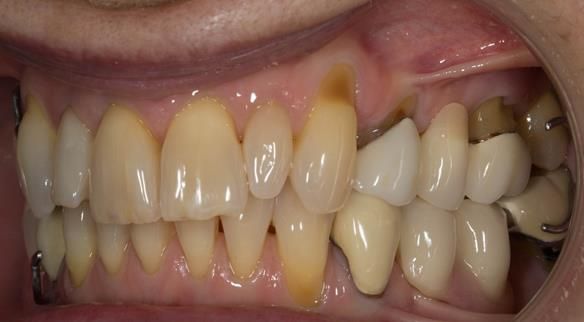

This newsletter describes in step by step detail Angela's transition through immediate partial dentures to crown supported definitive metal based dentures.

This 58 year old woman was referred to me by her general dental practitoner for treatment.

- Generalised Periodontitis; Stage 4, Grade C, Currently Unstable. Risk Factors: Type 1 diabetes. 16, 17 - hopeless prognosis. 14, 24, 26, 27, 34, 37, 44 - guarded prognosis

- Poor marginal fit and poor appearance of crowns and bridgework

The clinical situation and treatment process is shown in detail below with photographs. I (Finlay Sutton) provided the clinical work and Rowan Garstang provided the technical work.